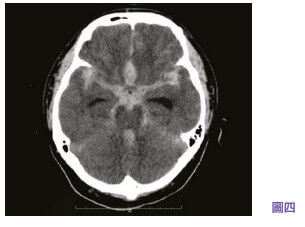

中风当时29岁的杨小姐14年前,当时29岁的杨小姐,身体健康过着正常的生活,一向没有头痛的症状。 就在新婚后三天的黄昏,丈夫放工回家后发现太太昏迷倒卧在地上,于是立即召唤救护车将太太紧急送到附近的公立医院。 脑部电脑扫描显示病人蛛网膜下腔出血性中风(见图一),怀疑是脑血管动脉瘤爆破,由于该公立医院没有脑血管外科,病人丈夫于是要求将妻子转往私家医院。